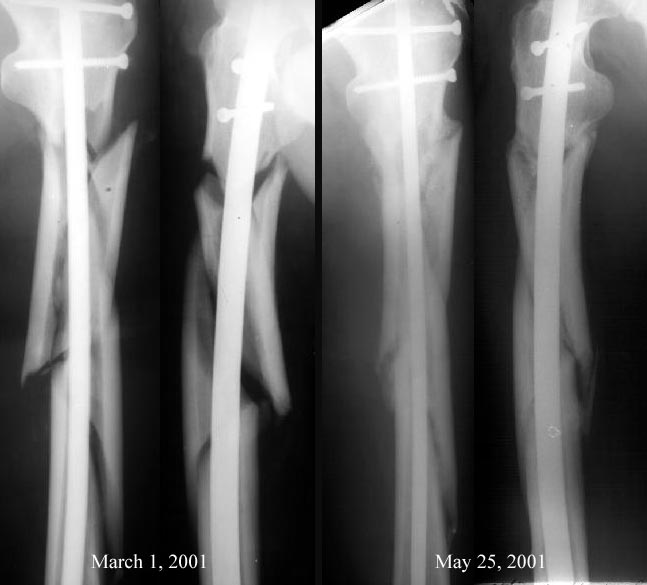

Вспоминается подобная ситуация в 2001 г., как раз сегментарный оскольчатый перелом бедра, тоже начальство упрекало в пренебрежении к принципам остеосинтеза, чуть не приказали повторно взять больного и скласть красиво все кусочки... Благодаря поддержке интернет-сообщества удалось отстоять, вскоре все замечательно срослось.

Вот тогдашняя картинка - после операции и через 3 мес.